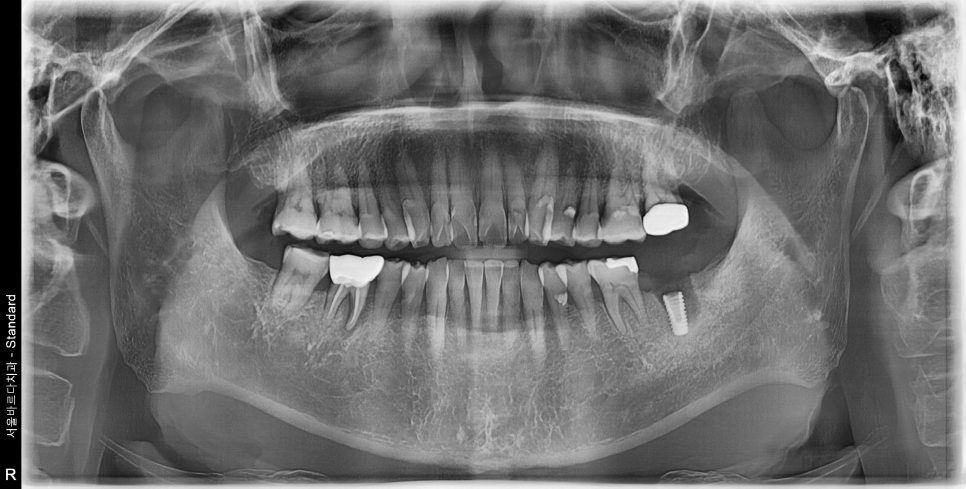

살포시 발치를 완료하고 남은 뿌리가 없는지

X-ray를 찍어봅니다.

남은 뿌리없이 깔끔하게 나왔네요.

다시 수술방으로 돌아와 바로 임플란트를 심기 시작합니다.

오래 걸리지도 않습니다. 임플란트의 각도와 깊이를 확인 한 후

매우 만족하며, 다음 단계인 뼈이식과 봉합을 진행합니다.

뼈이식과 봉합까지 모두 마무리한후 찍은 사진입니다.

(해당 케이스는 뼈이식을 하지않더라도

임플란트의 성능과 수명에는 문제가 없을 케이스입니다.

이런 경우 따로 뼈이식 비용을 청구하지는 않습니다.

본 환자분의 경우는 잇몸부위의 볼륨감과 풍융함을 형성하여

음식물이 치아 사이에 끼는 증상을 최소화하기위해

뼈이식을 진행하셨습니다.)

2달이 지났습니다. 임플란트가 잘 붙은것을 확인하고

임플란트 상부 보철물 제작을 진행합니다.

반대편에 고름주머니 잡힌 치아도 발치 즉시 식립으로 수술을 원하셔서

당일 수술 진행해 드렸습니다.